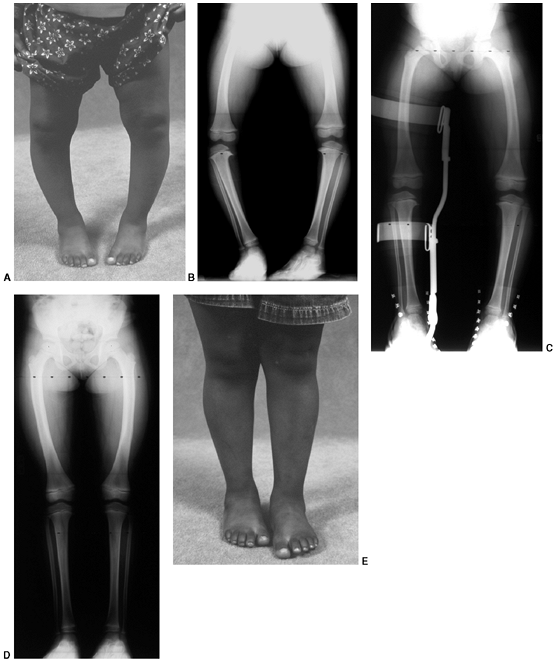

![]() |

Figure 28.13 A: This 30-month-old girl shows clinically asymmetric bowing. She is large for her age (>95% weight). B:

The metaphyseal-diaphyseal (MD) angle on the right is 20 degrees, compared to 10 degrees on the left. This is consistent with stage II changes of Blount disease on the right and physiologic bowing on the left. C: A transverse osteotomy is performed distal to the tibial apophysis. An appropriately sized wedge is removed to allow slight overcorrection. D: Smooth Kirschner (K) wires are used for fixation, supplemented with cast immobilization. E: Clinical alignment can be assessed using a bovie cord, which is visualized radiographically. The leg should be allowed to rest in its neutral position. F: Intraoperative films of a right proximal tibial osteotomy show slight overcorrection to valgus. A bovie cord centered over the hip and ankle is an easy method to assess mechanical axis intraoperatively. G: A clinical photo taken 2 years later shows maintenance of correction on the right. Spontaneous correction of physiologic bowing has occurred on the left. |

the medial tibial physis is less likely to occur if surgery is delayed (50,52,53,71,76) (Fig. 28.13 A,B).

deformity. The fragments are stabilized with smooth K-wires (Fig. 28.13 C,D). Alternatively, Price et al. (91)

without translation of the distal fragment laterally is desirable (50,52,53,92).

anteroposterior spot radiograph of the knee (Fig. 28.13 E,F).

It is essential to document that valgus alignment has been obtained and

examinations until skeletal maturity (Fig. 28.13G).